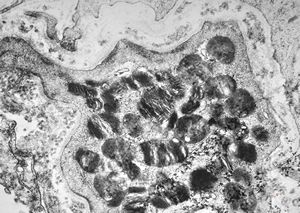

M, 6m. | Niemann-Pick disease - liver

M, 6m. | Niemann-Pick disease - brain